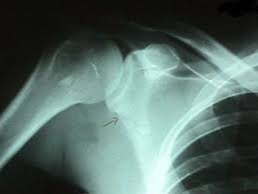

Q5. 골절 후 뼈가 잘 붙고 있는지 확인하는 방법은 무엇인가요?

A5. 가장 일반적인 방법은 정기적인 X-ray 촬영입니다. 회복 기간 동안 2~4주 간격으로 촬영하며, 뼈가 서서히 이어지는 골유합 상태를 확인합니다. 뼈가 제대로 유합되고 있다면 점점 뿌옇고 두꺼운 ‘골막’이 보이게 되고, 통증도 서서히 줄어듭니다. 간혹 유합이 잘 되지 않으면 초음파나 CT 검사를 병행하기도 합니다.